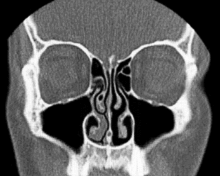

Según Heetderks, el ciclo es el resultado de la congestión y la descongestión alternas de los cornetes nasales, predominantemente los cornetes inferiores, que son, con mucho, los cornetes más grandes de cada fosa nasal. Los cornetes consisten en proyecciones óseas cubiertas por plexos cavernosos, que forman un tejido eréctil, al igual que los tejidos del pene y el clítoris. Los plexos venosos situados dentro de la mucosa que recubre los cornetes en una fosa se llenan de sangre mientras que los cornetes opuestos se descongestionan al ser desviada la sangre.[7]

Este ciclo, que está controlado por el sistema nervioso autónomo como se describe anteriormente, tiene una duración media de dos horas y media. Además observó y documentó que los cornetes en la fosa nasal dependiente se llenan cuando el paciente está en posición de decúbito lateral (acostado de lado). Algunos postulan que esta obstrucción posicional alterna tiene como propósito hacer que una persona gire de un lado al otro mientras duerme para evitar llagas.

En pacientes con una desviación septal fija y obstrucción nasal intermitente, la interacción del ciclo nasal se hace evidente; la sensación de obstrucción frecuentemente refleja la fase de congestión.[8]